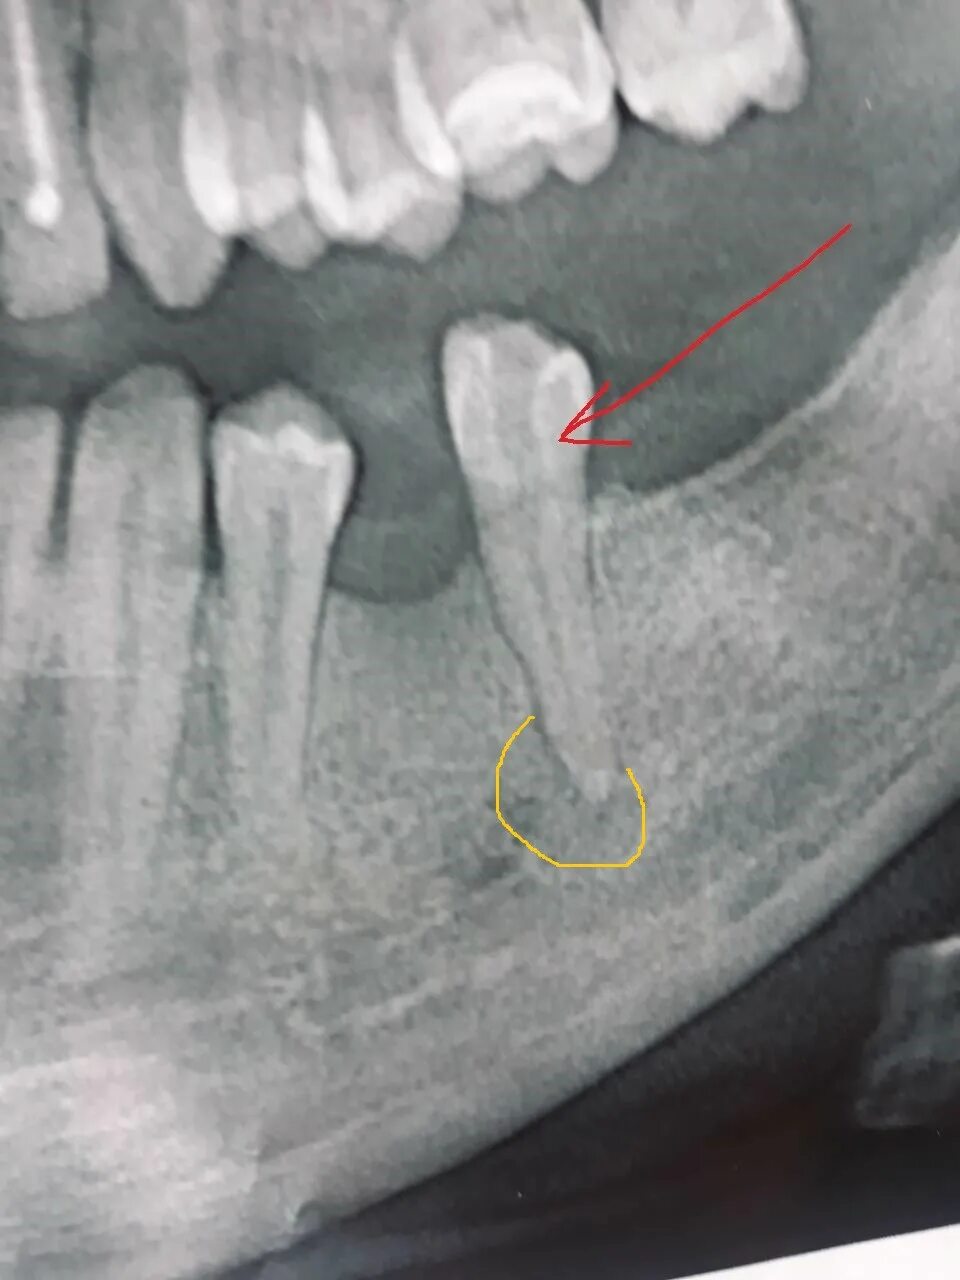

Киста зуба что это